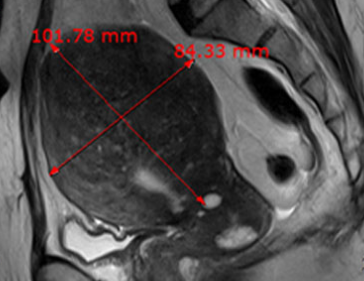

• 시술 전

시술 후